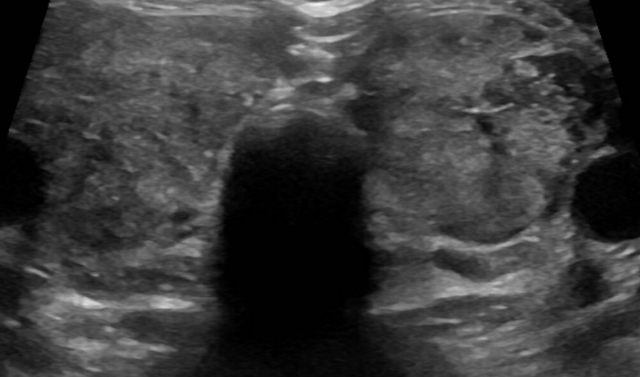

Hypothyroidism is a common endocrine disorder in which your child’s thyroid gland does not produce enough thyroid hormone. A ...